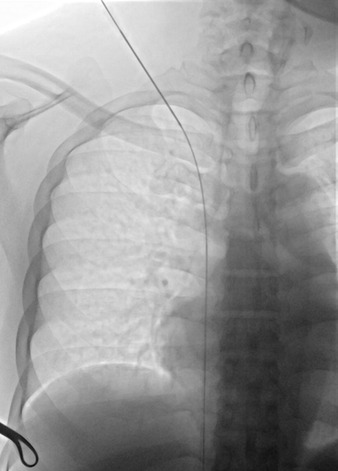

Background: Tunneled cuffed catheter (TCC) remains a crucial vascular access option for patients undergoing hemodialysis, particularly in those who are not candidates for arteriovenous fistulas or grafts. However, placement carries immediate and delayed complications. Objective: This narrative review aims to provide a comprehensive overview of the complications encountered during and after the placement of a TCC for hemodialysis, highlighting current evidence, risk factors, prevention strategies, and management approaches. Methods: A critical selection of relevant literature was performed through PubMed and Scopus databases, focusing on articles published in the last two decades. Particular attention was given to studies reporting on mechanical, infectious, thrombotic, and late-onset complications, as well as technical factors influencing outcomes. Results: Complications of TCCs can be classified as immediate (e.g., arterial puncture, pneumothorax, bleeding), early (e.g., catheter malposition, exit-site infections), and late (e.g., central venous stenosis, catheter-related bloodstream infections, thrombosis). Patient-and procedure-related factors increase risk. Ultrasound and fluoroscopy, strict sterility, and timely management reduce complications rates. Conclusion: TCCs are indispensable in selected patients, but understanding their complications is key to patient safety and outcomes. Optimal outcomes depend on accurate patient selection, operator expertise, and standardized post-placement care.